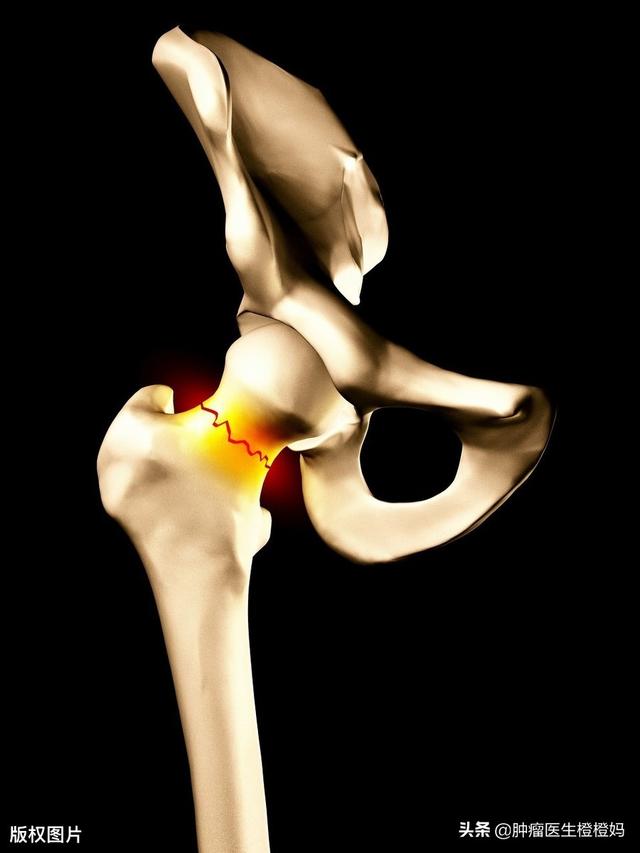

- Fractures pathologiques :Pourquoi parle-t-on de fracture pathologique ? Parce qu'il s'agit d'une lésion osseuse, c'est-à-dire d'une métastase osseuse suivie d'une fracture, contrairement aux fractures habituelles du type "bras cassé et jambe cassée". Lorsqu'une métastase osseuse se produit, la stabilité et la dureté de l'os ne sont plus aussi bonnes qu'auparavant, et de nombreuses personnes ne découvrent la présence d'une métastase osseuse que lorsqu'elles tombent accidentellement, se cassent un os et se rendent à l'hôpital pour y être examinées.Ce type de fracture se produit généralement dans les zones fortement sollicitées telles que le col du fémur et le fémur, c'est-à-dire l'os de la cuisse, est plus susceptible d'être plus fréquent.

Des fractures pathologiques peuvent également se produire lorsque des métastases se développent dans l'os, généralement dans les côtes, parce que les métastases détruisent la structure normale de l'os, le rendant faible et susceptible de se fracturer lorsqu'une force externe est appliquée. Certaines métastases osseuses peuvent également se présenter sous la forme de masses de tissus mous autour de l'os, mais elles ne sont pas faciles à détecter car elles ne sont pas à la surface du corps. Fracture pathologique (flèches ci-dessous)